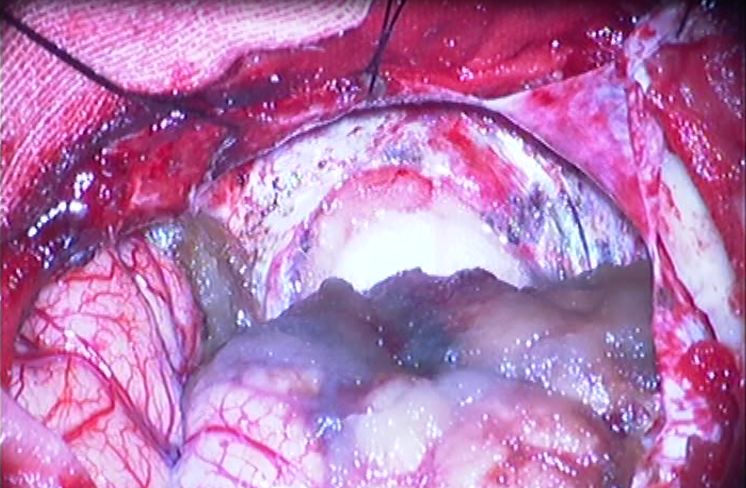

电灼肿瘤上壁及后壁交界处硬脑膜,锐性分离,彻底切除肿瘤包膜。

明胶海绵及棉条压迫控制出血。

止血纱及人工硬膜覆盖,术毕。